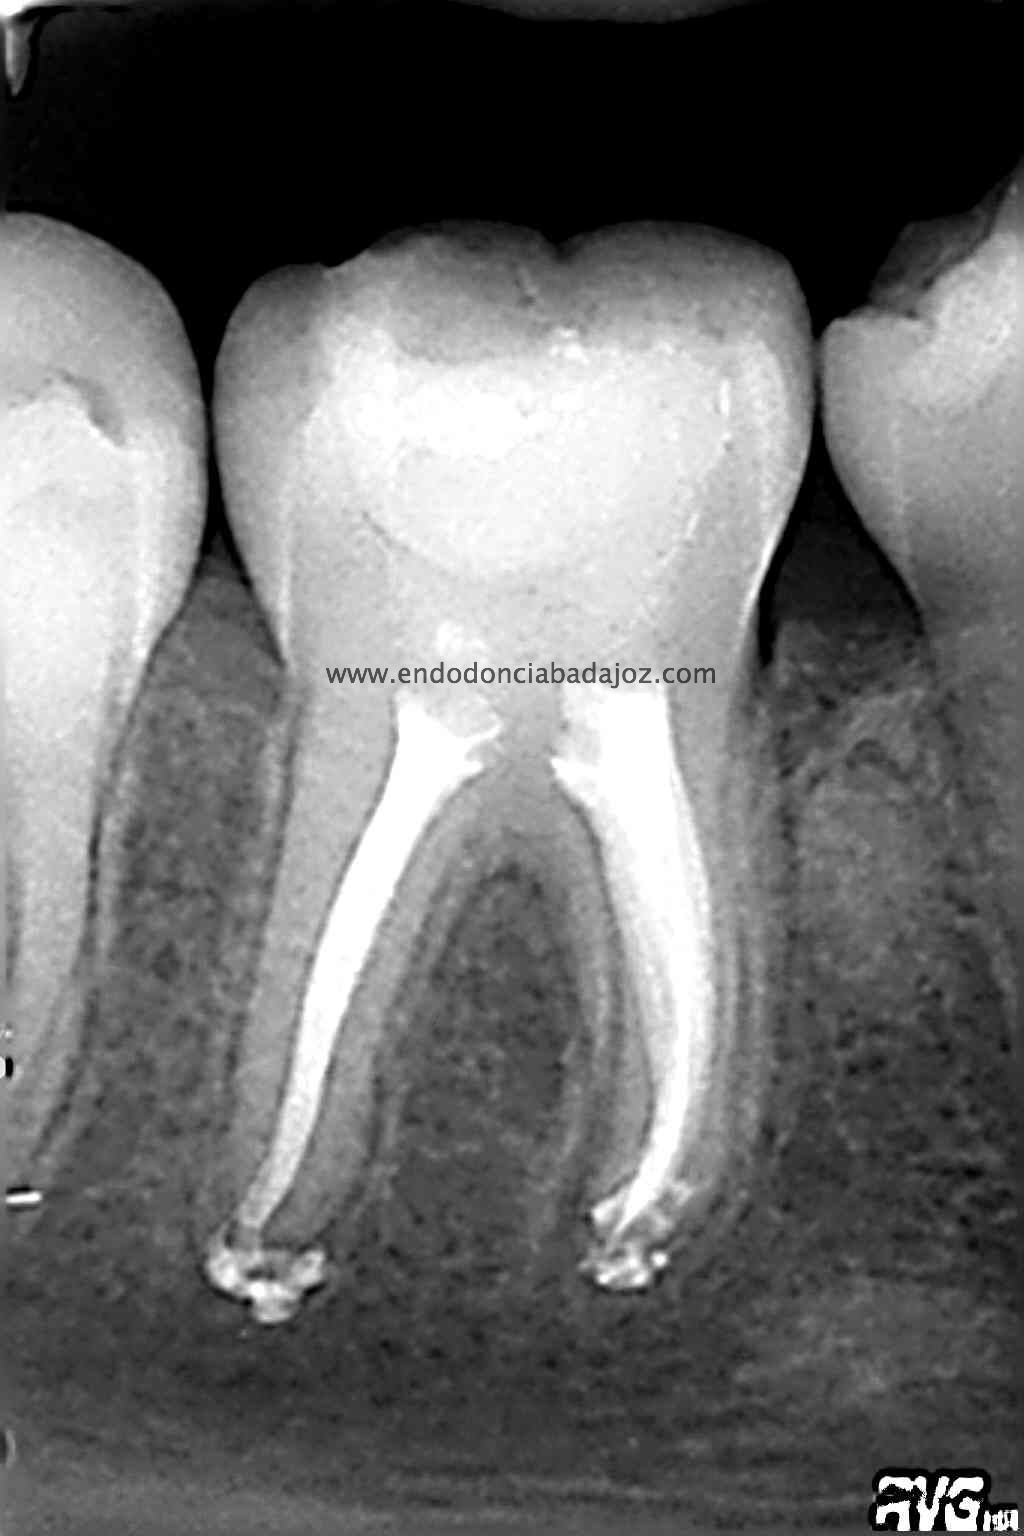

Se trata de un caso similar a este otro visto desde oclusal, observamos un istmo en la raiz mesial que tratamos como si fuesen varios conductos.

Una vez que hemos limpiado los conductos con un sistema de instrumentación  Protaper en combinación con limas K3. Pasamos a obturar los mismos con una técnica de condensación vertical de ola contínua de Buchanan y un backfilling con la gutapercha inyectada de la pistola ObturaII. Tomamos varias proyecciones, orto-mesio-distal

Con estas tres proyecciones nos quedamos mucho más tranquilos y seguros de un buen sellado hermético y tridimensional des sistema de conductos de esta pieza.